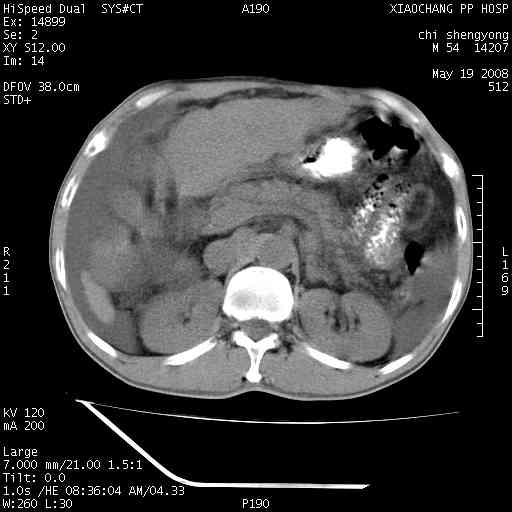

以下是引用zjzjr在2008-5-21 10:52:00的发言:[br]肝左叶巨块型肝癌伴门静脉左支瘤栓形成.肝硬化、腹水,胃底静脉曲张,脾术后改变。

以下是引用随光逐影在2008-5-21 16:20:00的发言:[br]1)肝左叶肝癌伴门静脉左支瘤栓形成,腹膜后淋巴结转移。2)肝硬化、腹水、胃底静脉曲张。3)胆囊炎。4)脾脏缺如,为切除术后所致。